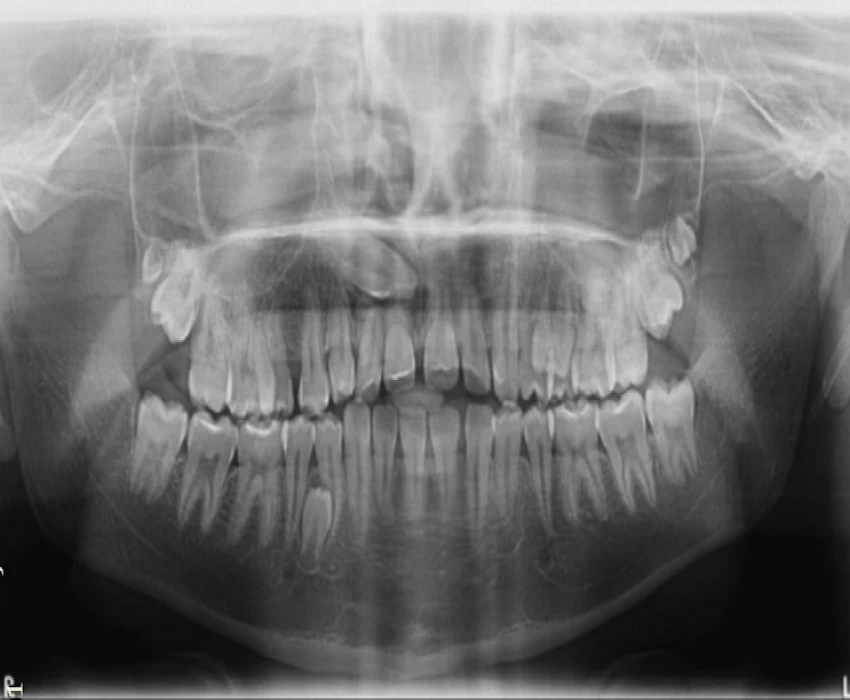

An OPG was taken which showed impacted permanent canine in the first quadrant, bunching of the teeth in the premolar area and supernumerary third molars in the maxillary arch on the both sides. An impacted mandibular premolar was observed in the fourth quadrant.

This is very unusual presentation of supernumerary teeth. As an essential diagnosis aid we usually go for OPG, Lateral cephalogram and PA Cephalogram; which gives us 2D presentation of the hard and soft tissue structures.

Another OPG was taken at this stage which confirmed the above findings.